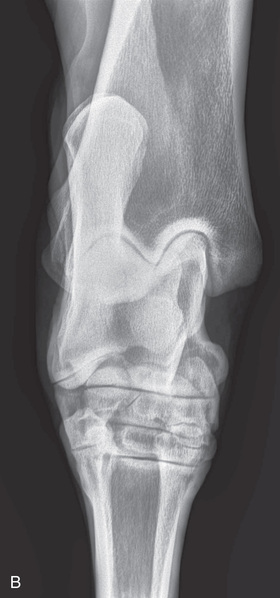

| Stifle | Lateromedial (LM) | Lateral (L) |

| Caudoproximal-craniodistal (CdPr-CrDi) | Caudocranial (CdCr) | |

| Lateral trochlear ridge and medial femoral condyle (stifle) | Caudoproximal 60-degree lateral–craniodistomedial oblique (Cd60L-CrMO) | CdLCrMO |

| Optional stifle | Cranioproximal-caudodistal (CrPr-CdDi) | Craniocaudal (CrCd) |

| Cranioproximal-craniodistal oblique(CrPr-CrDiO) | Skyline patella | |

| Lateromedial flexed (LM) | Flexed lateral (L) |

Radiography of the femorotibial joint (stifle) is difficult because of the thickness of the surrounding tissue and the sensitive nature of this region. Because of the depth of the muscle in the femoral region, the caudocranial projection demonstrates little above the joint space. Radiographs of this region should be attempted only if the patient is cooperative. Safety is paramount in radiography of the hind region of the horse. Sedation or a twitch may be used; general anesthesia is also to be considered.